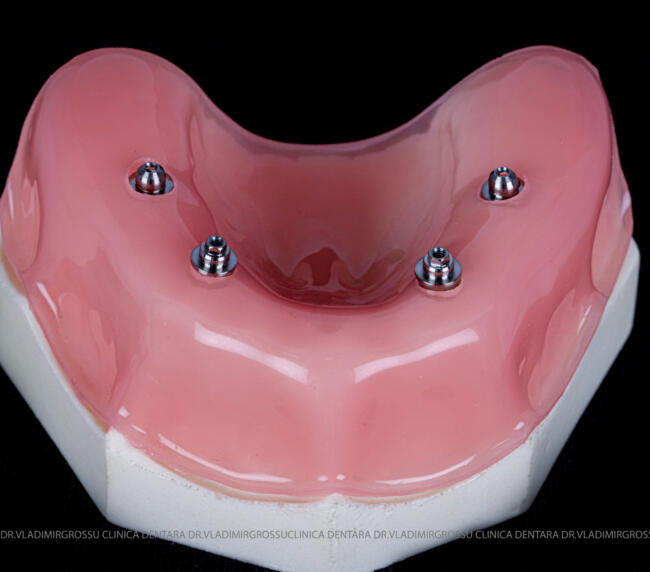

studii științifice.În cazurile de atrofie osoasă severă, când inserarea implanturilor în zonele laterale nu este posibilă fără adăugare osoasă, conceptul All-on-4 prevede plasarea implanturilor în unghiuri strategice pentru a evita zonele deficitare. Astfel, două implanturi sunt plasate în zona incisivilor laterali, iar alte două în zona premolarilor.

- 4 implanturi;

- 2 multiunit-uri drepte și 2 multiunit-uri angulate, conform necesităților protetice;

- 4 abutment-uri provizorii pe multiunit-uri;

- Proteză provizorie din masă plastică frezată sau proteză mobilizabilă pregătită și ajustată la componentele protetice.